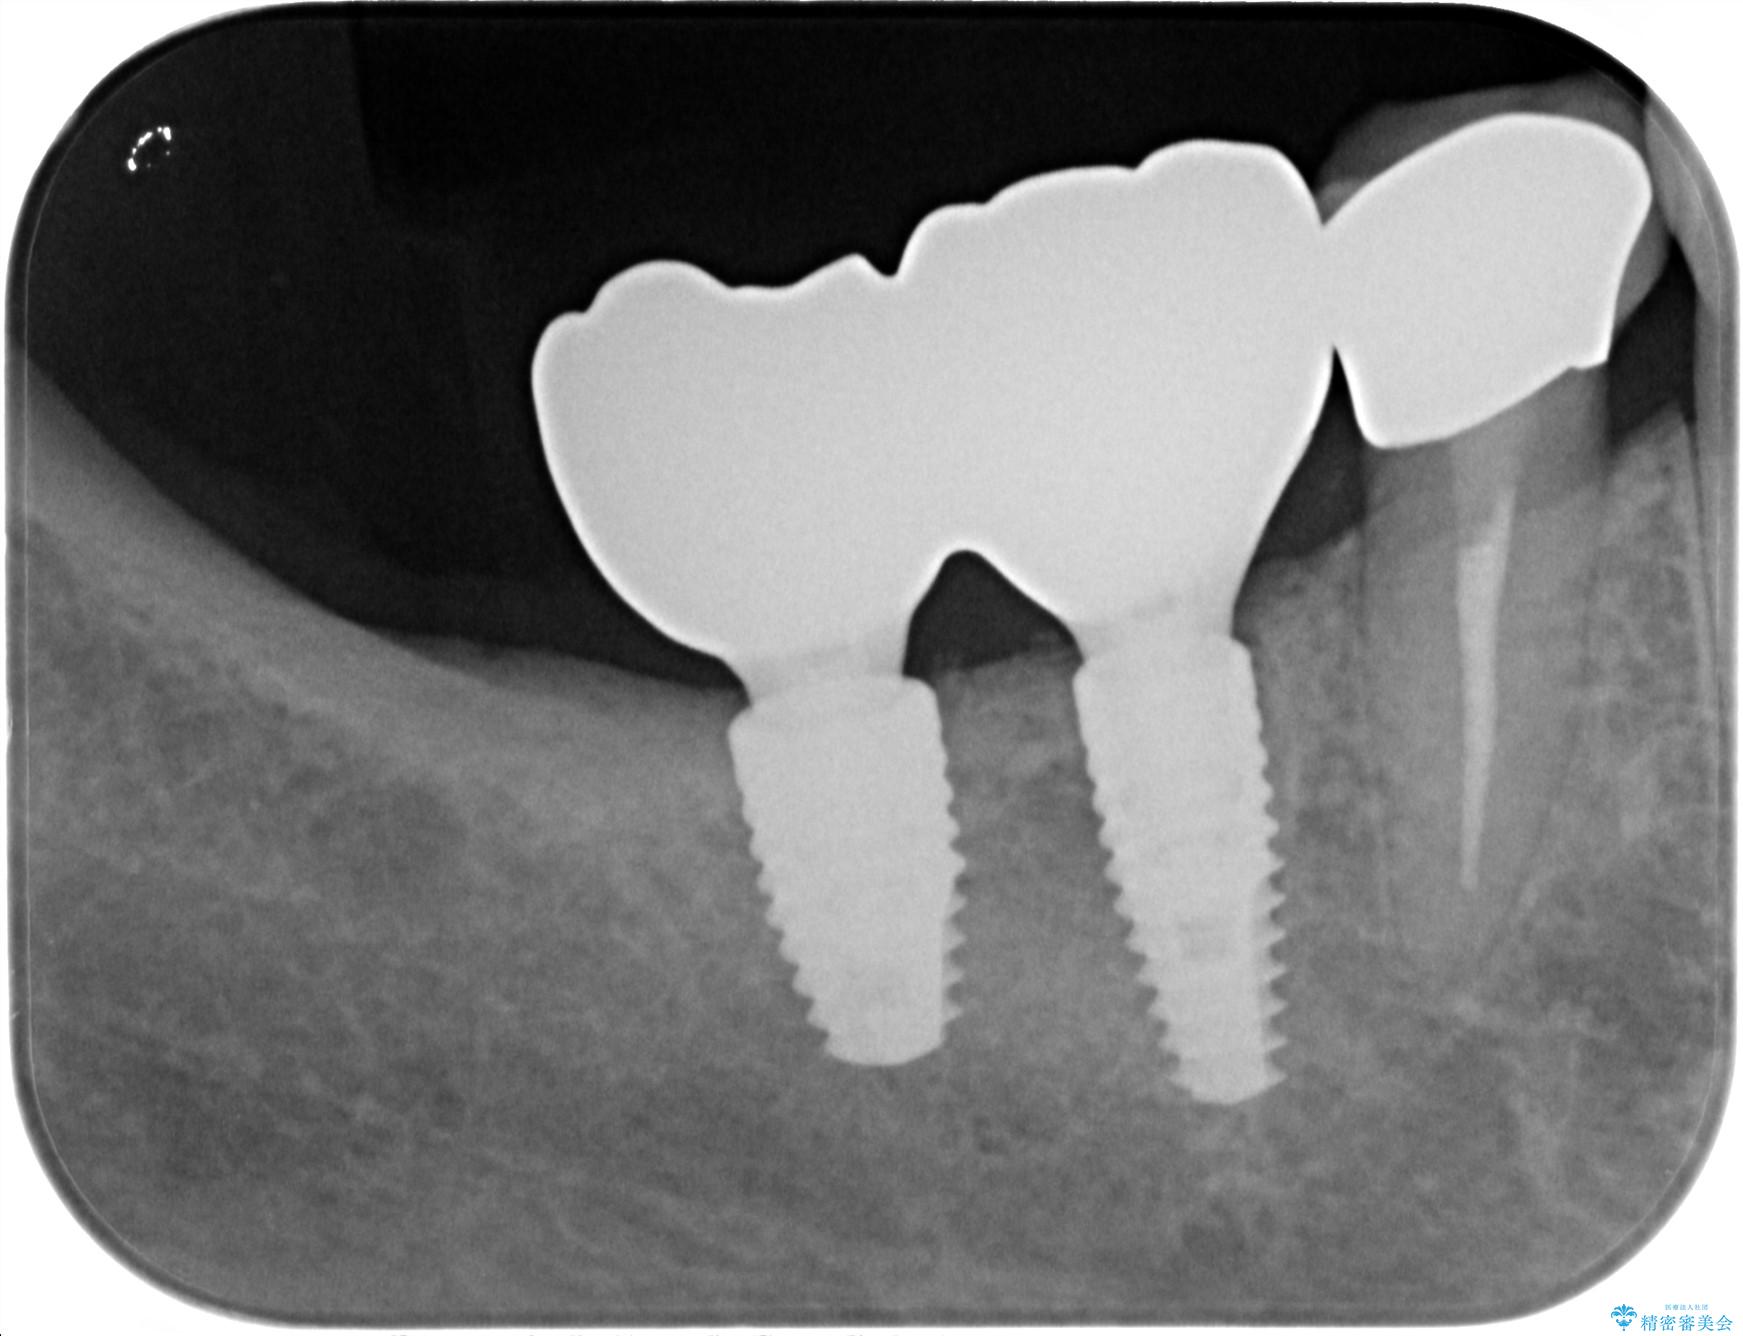

治療中

奥歯から膿のにおいがする インプラントによる機能回復 治療中画像 奥歯から膿のにおいがする インプラントによる機能回復 治療中画像 奥歯から膿のにおいがする インプラントによる機能回復 治療中画像 奥歯から膿のにおいがする インプラントによる機能回復 治療中画像